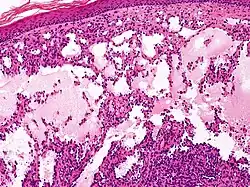

Lymphatic malformations (LMs) are congenital, benign slow-flow vascular malformations of the lymphatic system characterized by abnormally dilated lymphatic vessels that do not connect properly to the normal lymphatic circulation. These malformations represent developmental anomalies that occur during embryonic lymphatic system formation and are primarily caused by somatic activating mutations in the PIK3CA gene, found in approximately 75-80% of cases.[1]

Microcystic lymphatic malformations (formerly lymphangioma circumscriptum):

- Appear as clusters of small, translucent vesicles on the skin surface

- Range in color from pink to dark red

- May leak clear lymphatic fluid or occasionally bleed when ruptured